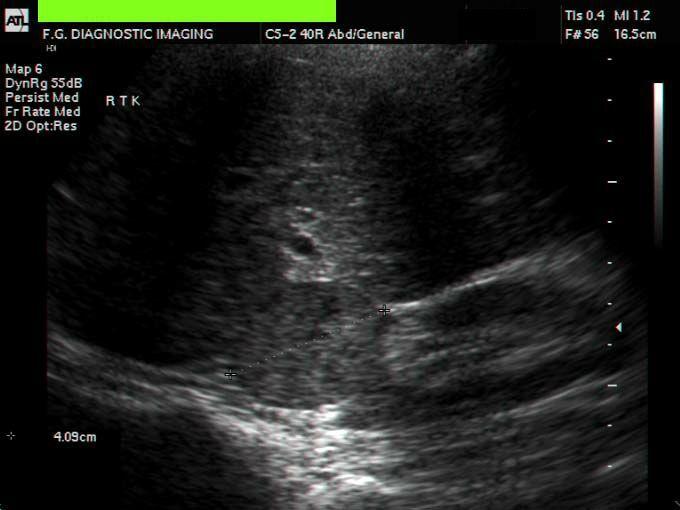

30 year old male presents for a renal ultrasound

liver & spleen cysts

Adult Polycystic Kidney Disease

infant presents with renal dysfunction

Infantile Polycystic Kidney Disease

results from cystic dilation of the collecting tubules